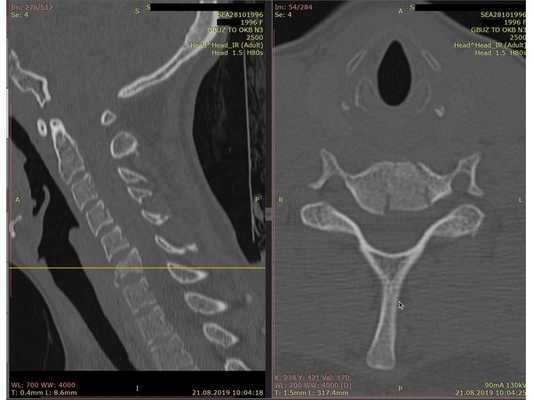

- Компьютерная томография шейного отдела позвоночника: выявлен компрессионно-оскольчатый перелом тела 6-го шейного позвонка (С6) и его дуги справа.

Контрольная КТ шейного отдела позвоночника на уровне тела позвонка С6. Виден установленный кейдж из пористого никелида титана и фиксирующая шейная пластина.

- Сформировали имплант из пористого никелида титана и установили между телами позвонков С5 и С7.

- Установили шейную пластину и зафиксировали 4 винтами: по 2 винта в тела позвонков С5 и С7. Выполнили рентген для контроля.

Через месяц на КТ шейного отдела позвоночника не было отрицательной динамики. При осмотре: неврологический статус без патологии, пациентка жаловалась на лёгкую осиплость голоса.